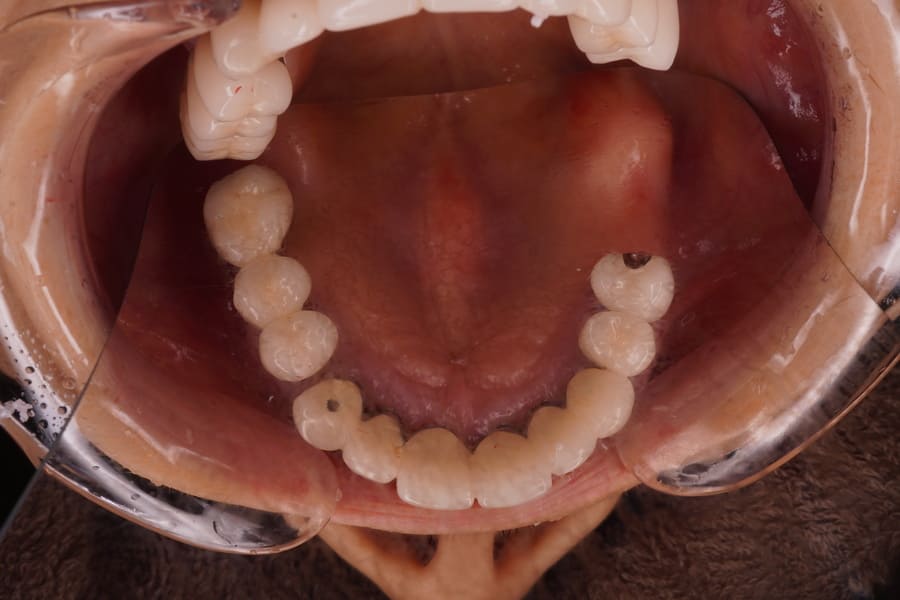

【症例概要】左上6,7番欠損。欠損放置後にノンメタルクラスプデンチャーを装着することにより審美的・機能的改善を図った

Before

左上6、7番欠損。 昔、入れ歯を作ったが近年使用していない。 左上6,7番欠損の顎堤の状態は骨、粘膜とも良好。 歯周組織は最大ポケット2㎜でエックス線所見においても問題となる骨欠損は認められず4,5番とも支台歯として適応可能と判断した。 補綴装置として義歯、インプラントいずれも適応可能であった。 各種補綴方法の利点・欠点・特徴・金額を説明した後、 患者さんの希望として、出来るだけ違和感がない物、見た目もあまり金属等で目立たないもの、落としても壊れにくい物であった。 これらのことを総合的に検討して、ノンメタルクラスプデンチャーの適応を提案し了解が得られたので製作することとした。 各種あるノンメタルクラスプデンチャーの材料の種類として、耐衝撃性が高く、透明感があり適合精度に優れたポリカーボネート系を選択した。 左上4番近心、5番遠心に明瞭なレストシートを設定することとした。 日本補綴歯科学会発行のノンメタルクラスプデンチャーガイドラインにもメタルレストの重要性が述べられている。 口腔内にて冠の一部を切削・研磨して明瞭な広さ、深さのレストシートを設置した。 印象採得、咬合採得を行った。 ろう義歯試適を行い咬合のずれ等問題がないことを確認した、 患者さんに鏡を見ながら着脱の練習をしていただき、ご自身での取り扱いが可能であることを確認した。 義歯の取り扱いや管理方法について説明を行った。 1か月後にリコールを行い問題がないことを確認した。 ノンメタルクラスプデンチャーによる欠損補綴 |